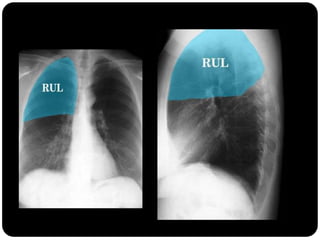

Atelectasia do lobo

superior direito

Atelectasia do Lobo Sup. D.

O que está anormal?

Atelectasia LSD

Sinal do S de Golden

Causado por

carcinoma

broncogênico

Note deslocamento

da fissura menor,

elevação da cúpula

diafragmática

direita...